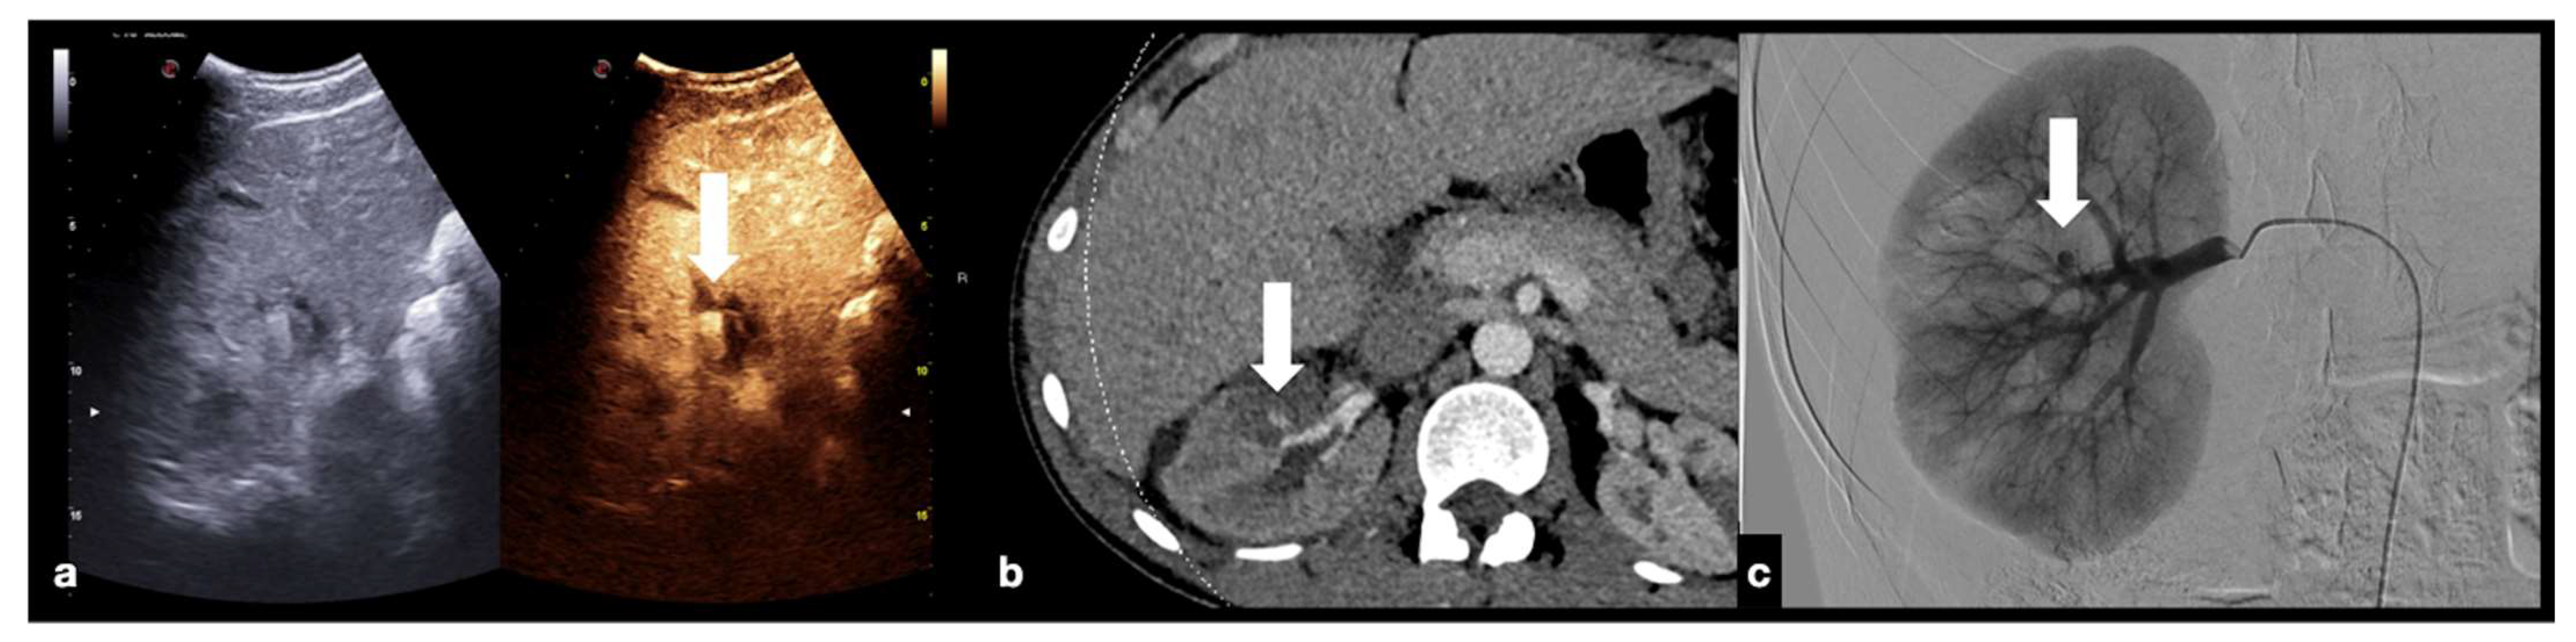

- Active bleeding:

- Contained vascular injuries: